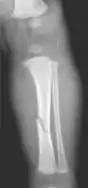

The material factual allegations of the amended complaint are as follows. Plaintiff was born on May 14, 1970. On repeated occasions during the first year of her life she was severely beaten by her mother and the latter's common law husband, one Reyes. On April 26, 1971, when the plaintiff was eleven months old, her mother took her to the San Jose Hospital for examination, diagnosis, and treatment. The attending physician was defendant Dr. Flood, acting on his own behalf and as agent of the defendant San Jose Hospital. At the time, the plaintiff was suffering from a comminuted spiral fracture of the right tibia and fibula, which gave the appearance of having been caused by a twisting force. Plaintiff's mother had no explanation for this injury. Plaintiff had bruises over her entire body. In addition, she had a non-depressed linear skull fracture which was then in the process of healing. Plaintiff demonstrated fear and apprehension when approached. Inasmuch as all plaintiff's injuries gave the appearance of having been intentionally inflicted by other persons, she exhibited the medical condition known as the battered child syndrome.

It is alleged that proper diagnosis of plaintiff's condition would have included taking X-rays of her entire skeletal structure, and that such procedure would have revealed the fracture of her skull. Defendants negligently failed to take such X-rays, and thereby negligently failed to diagnose her true condition. It is further alleged that proper medical treatment of plaintiff's battered child syndrome would have included reporting her injuries to local law enforcement authorities or juvenile probation department. Such a report would have resulted in an investigation by the concerned agencies, followed by a placement of plaintiff in protective custody until her safety was assured. Defendants negligently failed to make such report.

On this appeal plaintiff has expressly abandoned her claim of punitive damages. It is alleged that proper diagnosis of plaintiff's condition would have included taking X-rays of her entire skeletal structure, and that such procedure would have revealed the fracture of her skull. Defendants negligently failed to take such X-rays, and thereby negligently failed to diagnose her true condition. It is further alleged that proper medical treatment of plaintiff's battered child syndrome would have included reporting her injuries to local law enforcement authorities or juvenile probation department. Such a report would have resulted in an investigation by the concerned agencies, followed by a placement of plaintiff in protective custody until her safety was assured. Defendants negligently failed to make such report. The complaint avers that as a proximate result of the foregoing negligence plaintiff was released from the San Jose Hospital without proper diagnosis and treatment of her battered child syndrome, and was returned to the custody of her mother and Reyes who resumed physically abusing her until she sustained traumatic blows to her right eye and back, puncture wounds over her left lower leg and across her back, severe bites on her face, and second and third degree burns on her left hand.

While helpful, the foregoing general history of the battered child syndrome is not conclusive on the precise question in the case at bar. The question is whether a reasonably prudent physician examining this plaintiff in 1971 would have been led to suspect she was a victim of the battered child syndrome from the particular injuries and circumstances presented to him, would have confirmed that diagnosis by ordering X-rays of her entire skeleton, and would have promptly reported his findings to appropriate authorities to prevent a recurrence of the injuries. There are numerous recommendations to follow each of these diagnostic and treatment procedures in the medical literature cited above.

For example, the leading article by Kempe et al., op. cit., supra,[10] states that "A physician needs to have a high initial level of suspicion of the diagnosis of the battered-child syndrome in instances of subdural hematoma, multiple unexplained fractures at different stages of healing, failure to thrive, when soft tissue swelling or skin bruising are present, or in any other situation where the degree and type of injury is at variance with the history given regarding its occurrence . . . ." (Id., at p. 20.) Of the different types of fractures exhibited, an arm or leg fracture caused by a twisting force is particularly significant because "The extremities are the 'handles' for rough handling" of the child by adults. (Id., at p. 22.) The article also contains numerous recommendations to conduct a "radiologic examination of the entire skeleton" for the purpose of confirming the diagnosis, explaining that "To the informed physician, the bones tell a story the child is too young or too frightened to tell." (Id., at p. 18.) Finally, on the subject of management of the case it is repeatedly emphasized that the physician "should report possible willful trauma to the police department or any special children's protective service that operates in his community" (id., at p. 23) in order to forestall further injury to the child: "All too often, despite the apparent cooperativeness of the parents and their apparent desire to have the child with them, the child returns to his home only to be assaulted again and suffer permanent brain damage or death." (Id., at p. 24.)